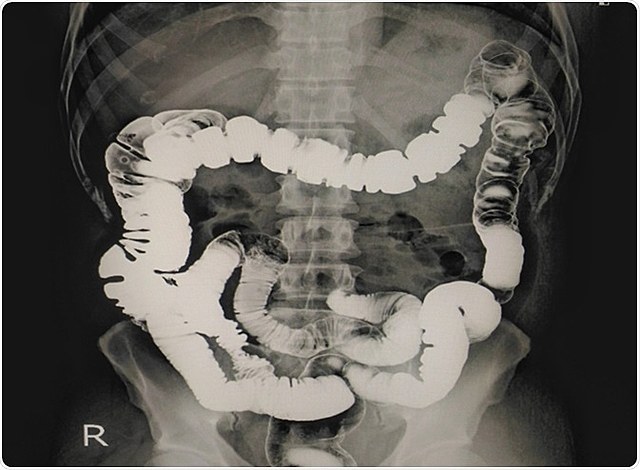

• Densitometría Ósea

Densitometría Ósea

J. Cameron y J. Sorenson descubrieron un nuevo método para medir de la masa ósea por absorciometría de simple fotón (ASF), que aún hoy en día conserva efectividad.